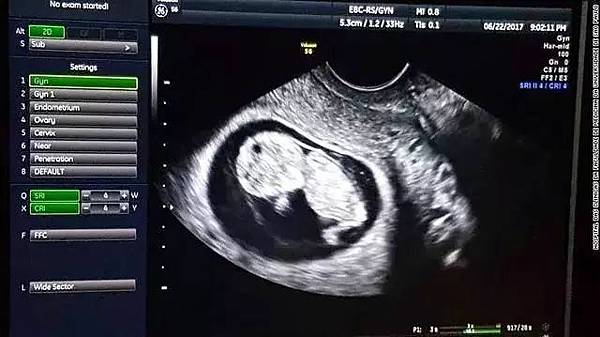

图为再灌注之后植入受者体内的子宫,白线标出处为子宫

本例接受移植的患者在术后37天来了月经,第二次在头一次的26天之后。在术后60天内发生过一次上呼吸道感染和一次阴道分泌异常,但都得到了有效的控制和治疗。患者在5个月后,B超检查显示移植子宫表现良好,患者月经正常,未见排异反应。